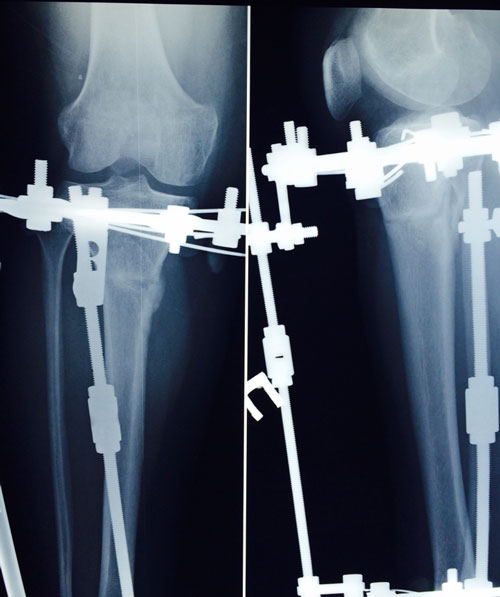

Ножки супер! разрешено всё без ограничений, все нагрузки: спорт, фитнес, каблуки любых размеров - Вам очень они пойдут! Нельзя: беременеть в течении первых 6 месяцев с момента снятия аппаратов!

Не забывайте про наш форум, высылайте фото ножек, пишите отзывы, нам это важно, это наша работа - искусство, которым мы гордимся!